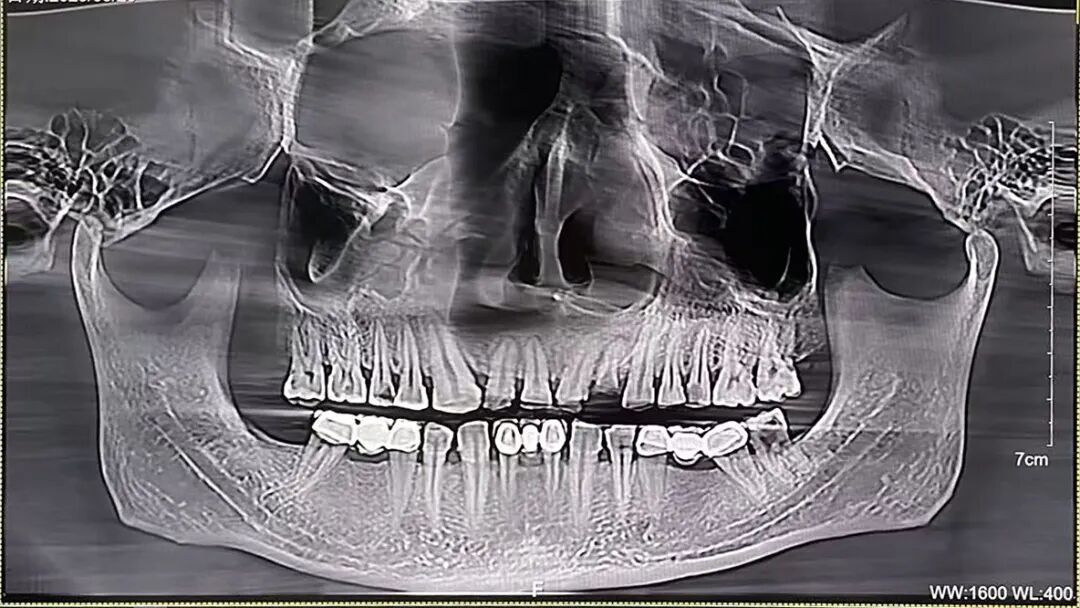

过去,传统牙片、全景片只能提供平面影像,像骨头密度、神经管位置这些关键信息,往往只能靠医生经验判断。

CBCT就像给口腔拍了一组“3D高清大片”,能清晰、直观地呈现口腔颌面部结构信息,为医生提供重要的诊断依据。

通过AI多阶段重叠对比功能,可模拟牙齿移动轨迹。对于错颌畸形患者,CBCT颅颌面骨骼三维重建精确展现上下颌骨与颅底相对结构关系,为正畸医生制定治疗计划提供精确影像学数据,并还能提前预测生长发育趋势及矫治效果,有效减少复诊调整次数。